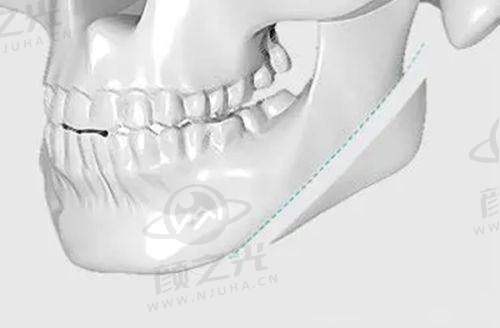

正畸医生团队:在牙齿矫正方面,也有非凡的医生坐镇。如针对骨性畸形病例,何锦泉医生主导的“正畸 - 正颌联合治疗”受深覆合患者肯定。正畸患者普遍对隐形矫正体验表示满意,也从侧面反映了医生的技术水平。

其他特色技术:正颌手术、笑氧无疼痛诊疗技术等也是该院的特色诊疗技术。